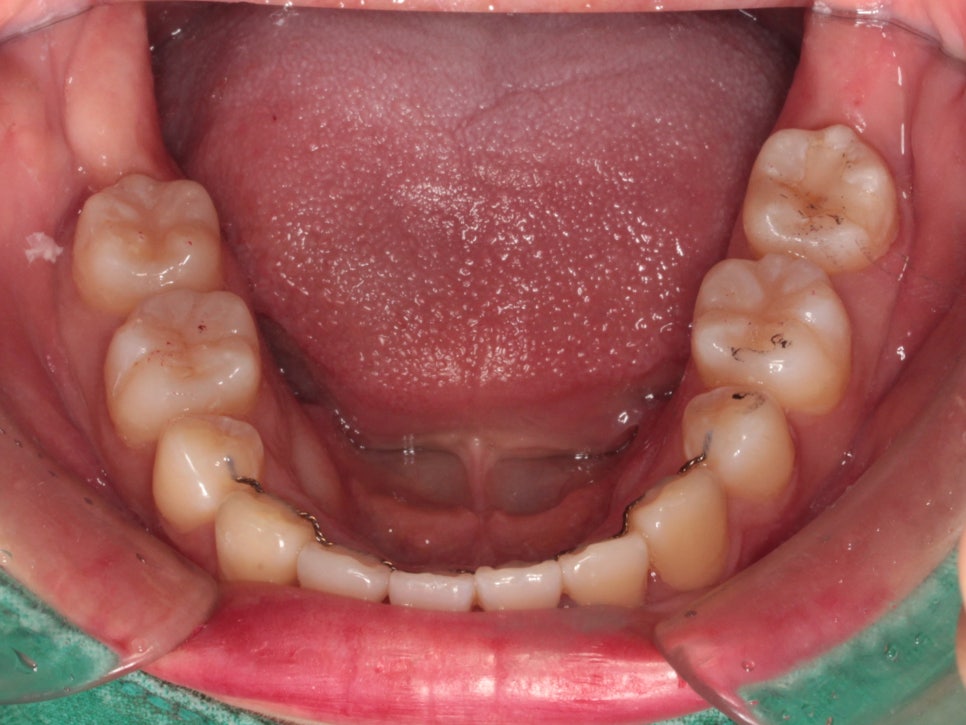

미니스크류를 식립 후 바로 찍은 사진입니다.

총 6개의 미니스크류를 식립하고 치료를 했습니다